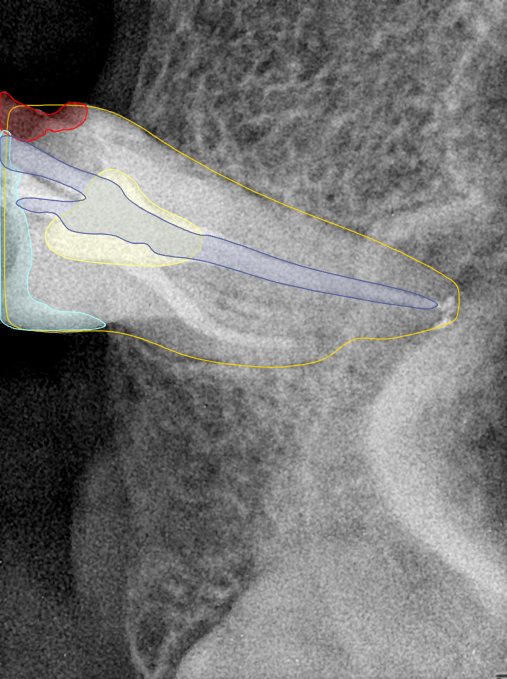

CR/DR 牙齿分割阶段记录

当前进展

- 完成了 CR/DR 牙齿相关分割训练

- 当前结果已经达到阶段预期,但仍有细节问题需要继续处理

相关测试

遇到的问题

- 训练过程中出现过 mask 下移问题

- 部分结果会出现 box 填充异常

- mask 边缘仍然有比较明显的锯齿感

第二版算法问题测试

| 第一版 | 第二版 | 是否解决 | |

|---|---|---|---|

![]() | ![]() ![]() 边角识别有问题 龋齿识别不全 牙髓识别不全 | ![]() | 解决 |

![]() | ![]() 边角识别有问题 识别信息有误 自查(牙冠识别不全) | ![]() | 解决 |

![]() | ![]() ![]() 边角识别有误 大范围填充识别遗漏 | ![]() | 解决 |

![]() | ![]() 识别信息不全 | ![]() | 解决 |

![]() | ![]() ![]() 边角问题 牙胶识别不全 牙冠识别不全 | ![]() | 解决 |

![]() 换图片 | ![]() | ![]() 牙冠部分稍微白了一些就识别成小范围修补,部分判断异常 | 部分解决,修复类略敏感,牙冠部分稍微白了一些就识别成小范围修补,部分判断异常。 |

![]() | ![]() ![]() 牙冠识别不全 牙髓不全 根尖炎龋齿识别有误 | ![]() | 解决 |

![]() | ![]() | ![]() | 解决 |

![]() 换图片 | ![]() | ![]() | 解决 |

![]() | ![]() 牙冠识别有误 | ![]() | 解决 |

![]() 换图片 | ![]() ![]() 边角识别有误 | ![]() 修复类敏感 | 部分解决,图像过白,导致修复类判断异常。 |

![]() 换图片 | ![]() 牙冠识别不全 | ![]() 修复类敏感 | 部分解决,图像过白,导致修复类判断异常 |

结论:修复类出现了不鲁棒的情况,后续需要加入轮廓的扩充数据进行增强。